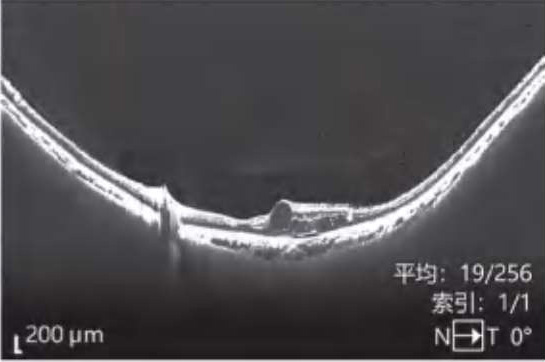

图2-2-1 抗VEGF及PRP治疗后玻璃体后脱离范围显著扩大的PDR案例

A.PDR合并玻璃体视网膜牵拉引发的相关DME,既往已行PRP,行4次抗VEGF药物治疗后,黄斑区玻璃体后界膜与视网膜分离(白色箭头所示),玻璃体视网膜牵拉解除,黄斑水肿较前明显好转。B.PDR合并玻璃体视网膜牵拉性相关DME,在行3次视网膜激光光凝治疗后,黄斑区玻璃体后界膜与视网膜分离(白色箭头所示),玻璃体视网膜牵拉缓解,黄斑水肿较前好转。